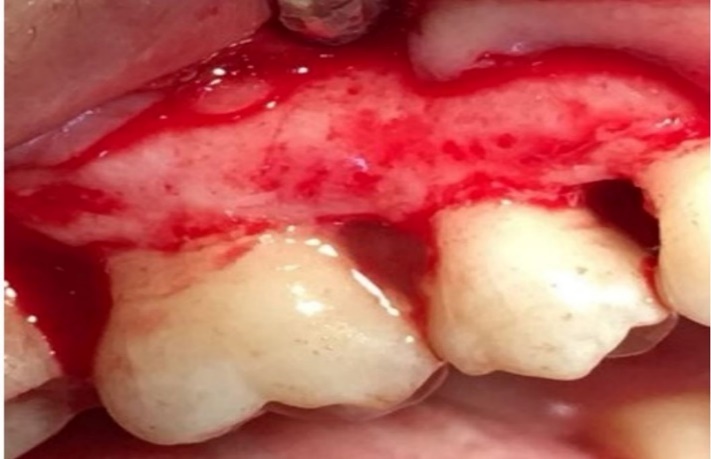

Defect zone containing metformin.

-

Group 3 underwent debridement and then the lesions were fully filled with PRGF gel (Figure 2); and in group 4 after debridement, first 1% MF biofilm was placed in the PRGF gel to intake gel and then the biofilm was packed into the lesions and PRGF gel was placed in the lesions over the biofilm (Figure 3).